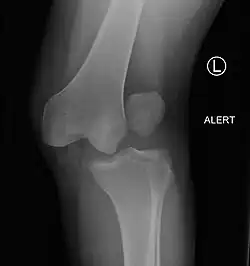

| Plain lateral X-ray of the left knee showing a posterior knee dislocation[1] | |

Plain X-rays, CT scan, ultrasonography, or MRI may help with the diagnosis.[2][11] Findings on X-ray that may be useful among those who have already reduced include a variable joint space, subluxation of the joint, or a Segond fracture.[5]